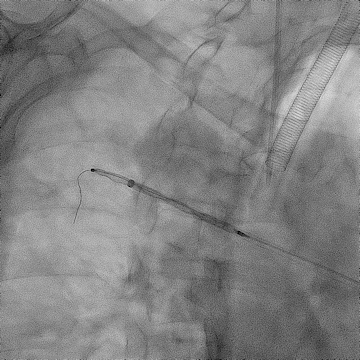

手术过程(一):

右股静脉穿刺,交换8 F-90 cm长鞘导入A3段,造影见A3段远端显影良好,中段动静脉瘘高速血流,可见“瘤槽”显影。